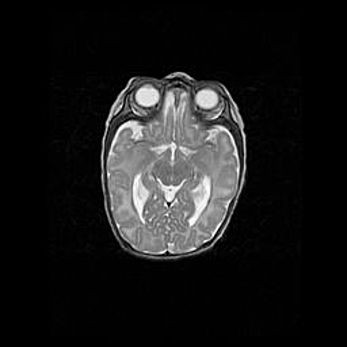

Церебральная ишемия II.

Возраст: 5 дней

Вес: 3400 г

Пол: женский

Окружность головы: 35 см

Срок гестации: 39 недель

Церебральная ишемия – это заболевание, характеризующееся недостаточностью (гипоксией) либо полным прекращением (аноксией) снабжения мозга кислородом по причине закупорки одного или нескольких сосудов. Это приводит к  что метаболическим расстройствам различной степени тяжести в тканях головного мозга, развитию коагуляционных некрозов и гибели нейронов.